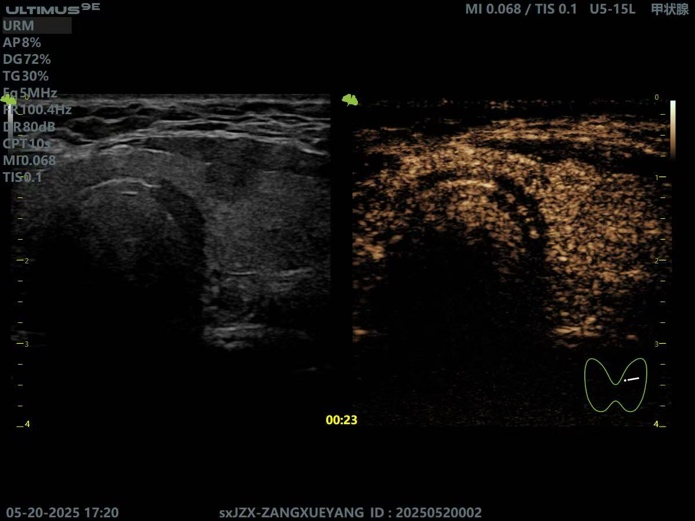

甲状腺左侧叶结节消融术后所见

超声造影术前